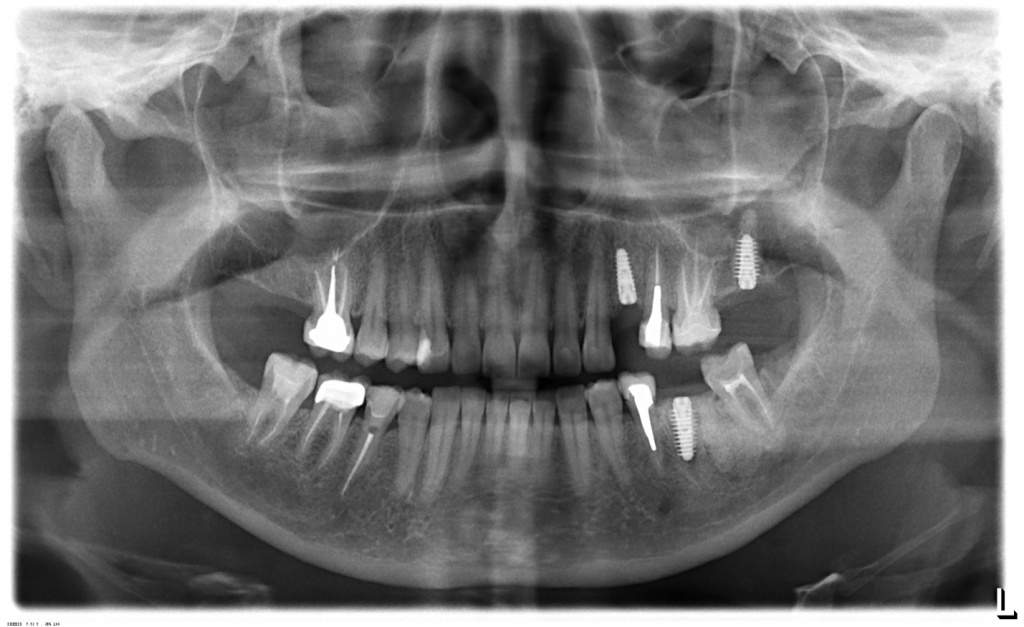

Ортопантомограммы пациентов до и сразу после имплантации. В 1-ом случае имплантат в позиции 36 и 27 , а на 2-ом снимке часть имплантатов установлены немедленно после удаления зубов.

CASE № 2

На нижней челюсти планируется установка условно-съемного протеза на балке. После протезирования на нижней челюсти планируется решение вопроса о протезировании на верхней челюсти (по настоянию пациента сроки раздвинуты).

Имеется не один снимок, где наглядно можно в этом убедиться. На верхней челюсти 6 специфичных корейских имплантатов AnyRidge, премиум класса, позволяющих без костных пластик сделать временные зубы в тот же день (тем самым сэкономив время и деньги на костной пластике). На нижней челюсти 3 немецких имплантата Impro - классическая и приятная в работе система.